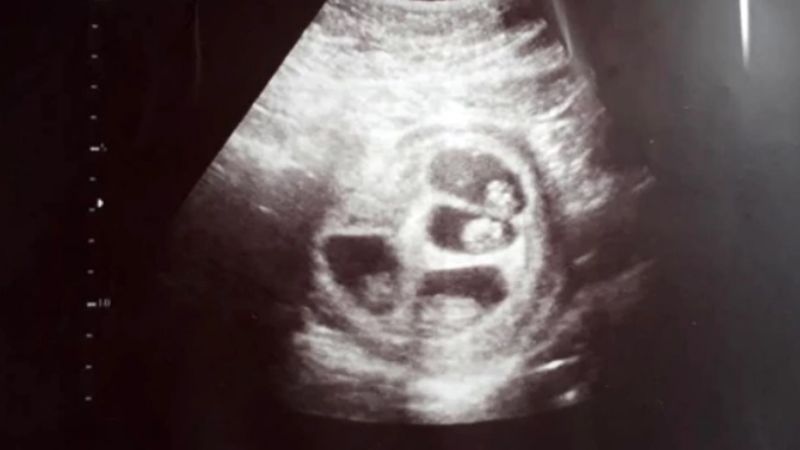

"Así que fuimos a hacer la ecografía. La ecógrafa me puso el gel en la panza y, apenas miró el monitor, se le transformó la cara. Miraba la pantalla, abría grande los ojos y repetía: 'No puede ser'. No dijo nada y salió a buscar a más médicos", cuenta. "Miré la pantalla y pensé que era cáncer, pensé que todo eso que se veía eran tumores y no había sabido cómo decírmelo".

Luciano se quedó en silencio cuando su novia lo miró asustada. "Yo también pensé que le habían encontrado una enfermedad", confiesa a Infobae. La ecógrafa volvió a entrar al consultorio acompañada de un obstetra y otra especialista en diagnóstico por imágenes. "Decían 'no puede ser, mirá', 'uhh' 'siii, es así', 'nunca vi algo así'. Estaba tan asustada que no me animaba a preguntar".

Cuando se animó a preguntar qué estaba pasando, la respuesta fue: "Bueno papis, están esperando cuatro bebés. Parece que dos son gemelos y los otros dos son mellizos". Jéssica empezó a llorar: "Pensé 'mi mamá me mata'. Estuvimos todo el viaje de vuelta pensando excusas, porque le habíamos dicho que íbamos al gastroenterólogo. Pero se ve que ella ya sospechaba y nos estaba esperando en la puerta".

La siguiente ecografía mostró que cada uno estaba gestándose en una bolsa diferente. Y pese a que le dijeron que era probable que pasara el embarazo internada y que alguno de los cuatrillizos no llegara a desarrollarse, los bebés -dos varones, una nena y un dudoso- están mejor de lo que esperaban. El más grande ya pesa 1,405 kg, el que sigue 1,210 kg., el otro 1,200 kg. y la nena 957 gramos.